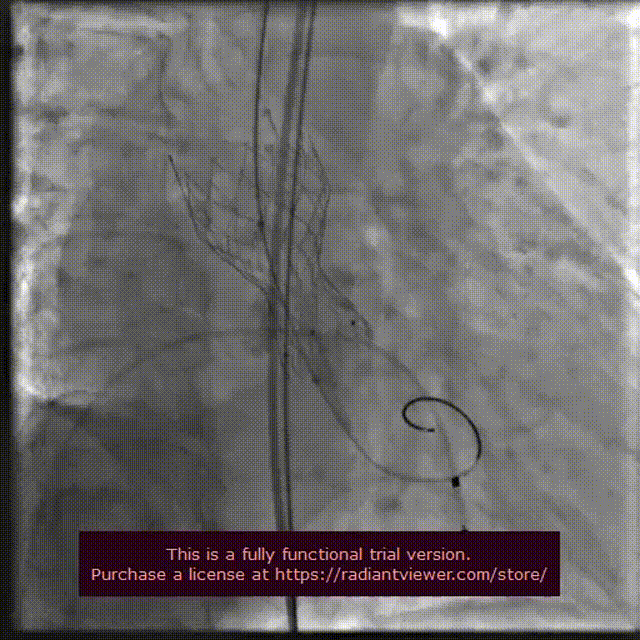

输送系统定位

VenusA-Plus®释放过程

18 mm球囊后扩